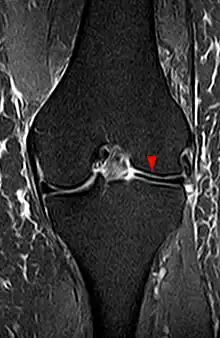

Discoid meniscus on coronal proton-density weighted MRI

The transverse diameter of a normal meniscus is approximately 10 to 11 mm; therefore a normal meniscus body will be visible on only 2 slices of a MR with 4-5-mm sagittal slices. A discoid meniscus should be considered if more than two contiguous body segments are present. However, this method may lead to a false negative when evaluating people with the Wrisberg variant of discoid meniscus since it maintains a narrow crescent shape. Coronal and radial images of the meniscus are useful to demonstrate the extension of the aberrant meniscus into the joint as seen here. On coronal images, it is diagnosed when the horizontal measurement between the free margin and the periphery of the body is more than 1.4 cm.[2] Rarely, X-ray may show lateral joint space widening, squaring of the lateral condyle, cupping of the lateral tibial plateau and hypoplasia of the lateral tibial spine that suggest discoid meniscus.